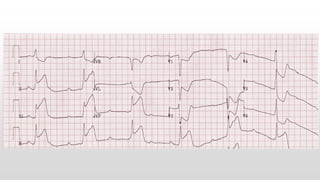

This document discusses various cases of collapse and syncope. It defines collapse as transient loss of consciousness with loss of postural tone and full recovery. Syncope is defined as loss of postural tone with or without loss of consciousness and full recovery. It then discusses the multiple potential causes of collapse and syncope including toxicological, cardiac conduction abnormalities, structural cardiac issues, autonomic dysfunction and more. It then goes through 9 case examples, discussing important questions to ask, potential tests and interventions for each case.